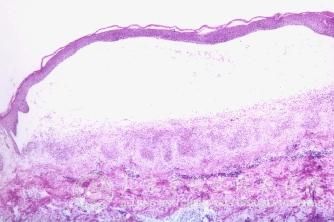

怎么预防植物性皮炎?植物性皮炎是一种常见的疾病。很多人对过植物性皮炎的关注就是必要的。了解植物性皮炎的相关注意事项,可以让植物性皮炎患者朋友 的配合医生的治疗,以达到 的植物性皮炎治疗结果。为此,北京京城皮肤医院将会详细介绍怎么预防植物性皮炎,希望可以帮助患者朋友早日摆脱植物性皮炎。

北京京城皮肤医院指出:植物性皮炎患者以青壮年女性多见,同一家庭里往往有相同的病人发生。尽量避免过多服食和接触有光感作用的植物,同时应避免日光的直接照射。亦可用改善烹调方法,在所食某些蔬菜或野菜内,酌加适量食醋后再烧煮。